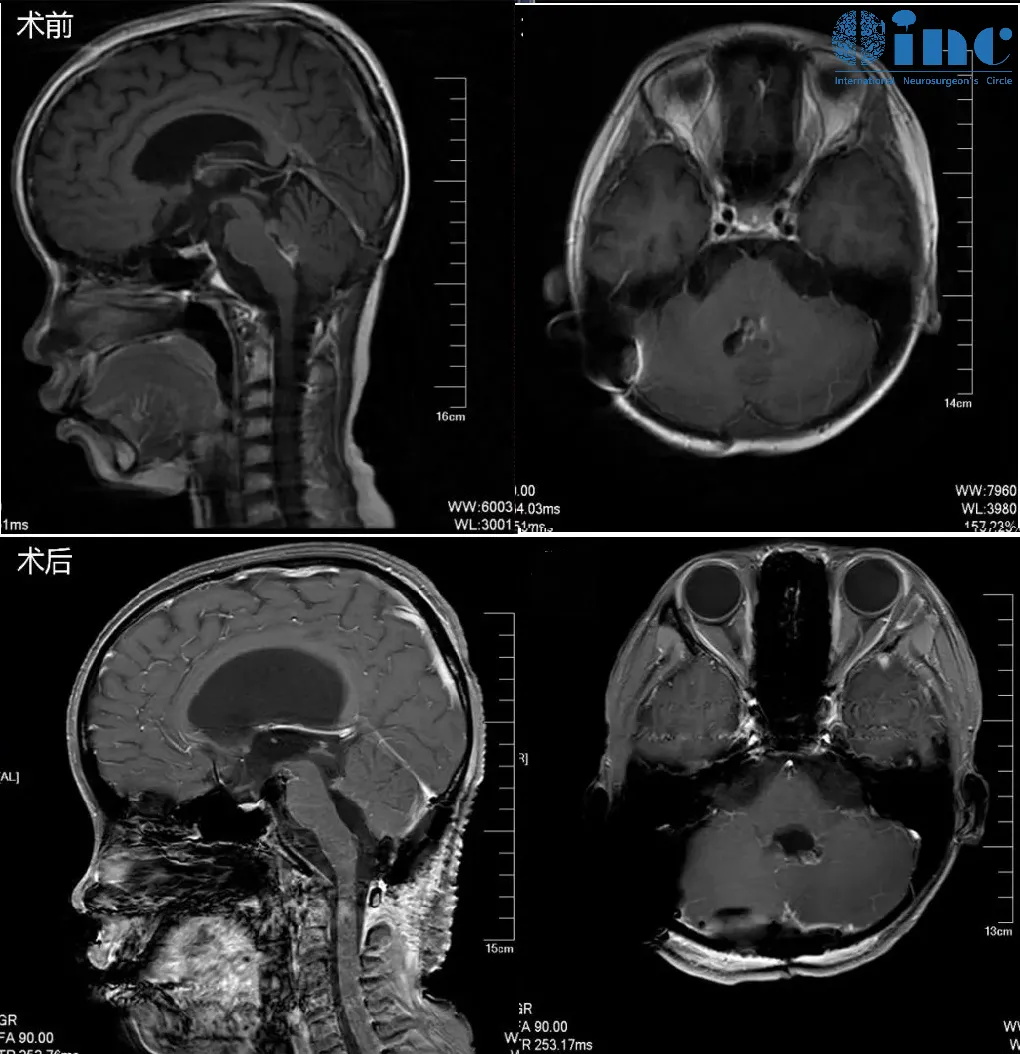

▼在苏州大学附属儿童医院,巴教授已经顺利为周周顺利完成手术,顺利全切四脑室肿瘤。

“感谢巴教授!感谢INC的!感谢苏州儿童医院的大力支持!今天收到了较好的消息,手术效果很好,可以出院了,王王任说了一句可以长期生存是我听医生说的较动听的话!真的是很激动的,别说能养活一百年了,能看着长大陪我们变老,一个正常人的生活就好。今天感受了一下喜较而泣,真是感谢你们做的全部努力,才能让我感受到儿子生的希望。”

——10岁脑干及四脑室肿瘤患儿父亲

▼顺利出院前一天周周父母向INC工作人员发来感谢

▼术后2天,巴教授到病房探视小病人

从悲观绝望,只求儿子多陪他们几年;到喜较而泣,孩子获得了新生,可以像正常人一样长期生存,这是父母听到的较动听的话。